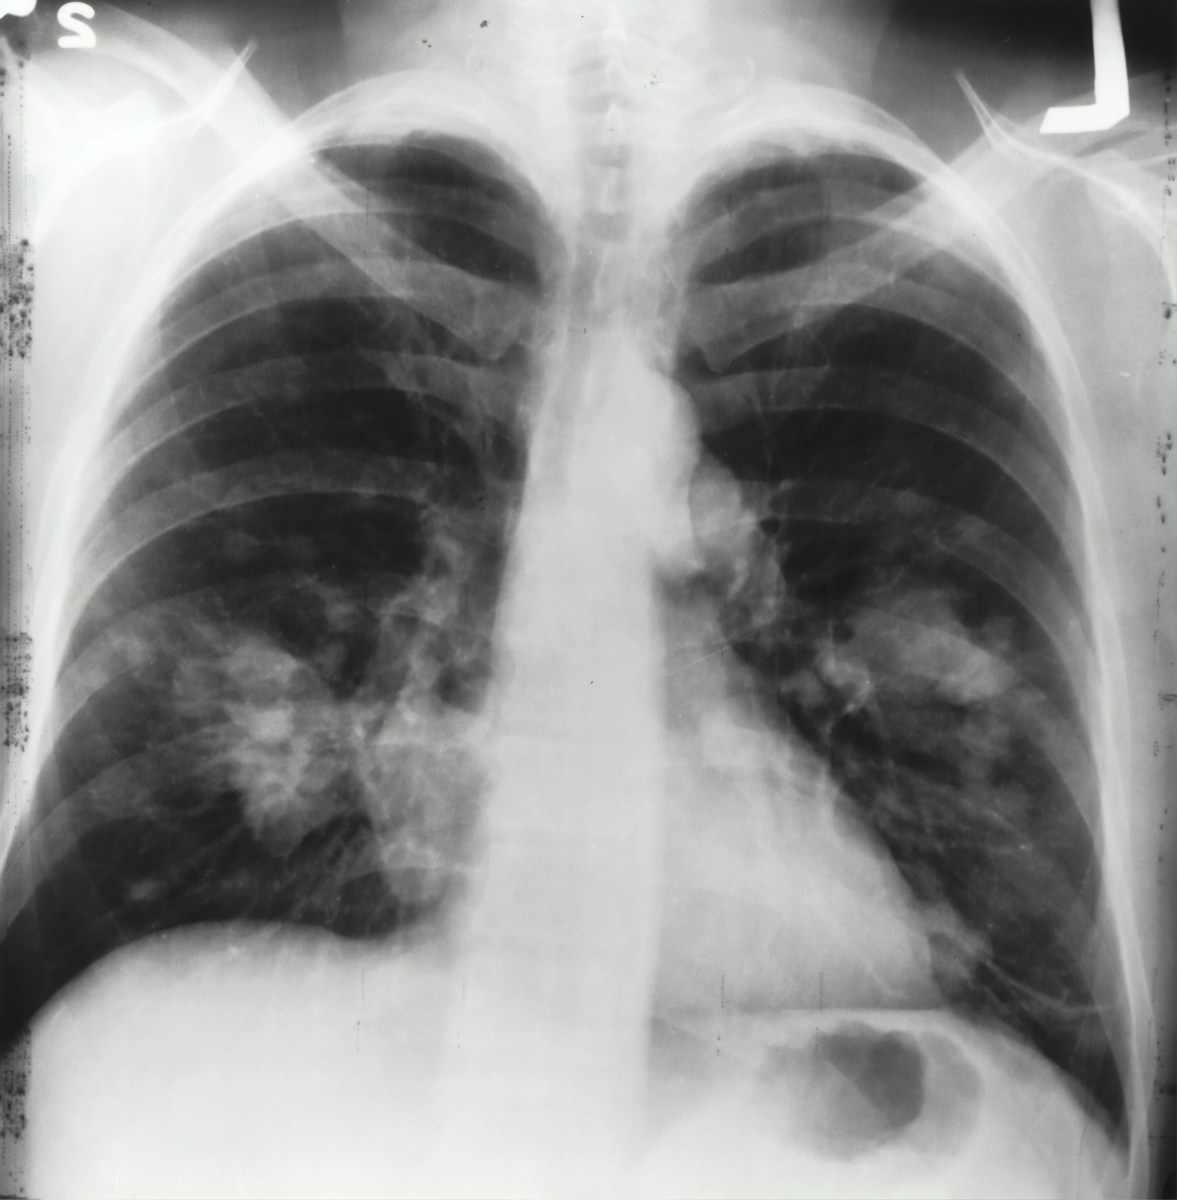

La polmonite si manifesta come un’infezione respiratoria che coinvolge gli alveoli polmonari. Tra i sintomi principali figurano tosse persistente, febbre alta, brividi, e fiato corto. L’insufficienza respiratoria e l’emoftoe, ovvero lo sputo sanguinolento, possono indicare casi più gravi.

La differenza tra polmonite e broncopolmonite risiede nella localizzazione dell’infezione. La broncopolmonite colpisce multipli focolai alveolari, mentre la polmonite lobare interessa una parte specifica del polmone. Il riconoscimento della specifica natura dell’infezione è cruciale per il trattamento corretto. Esami come quello dell’escreato aiutano ad identificare il patogeno responsabile, guidando la scelta dell’antibiotico più efficace.